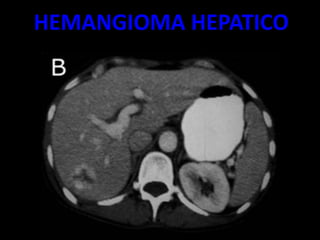

HEMANGIOMA HEPATICO

– EL MÁS FRECUENTE ES EL ANGIOMA.

SE TRATA DE UNA LESIÓN

ASINTOMÁTICO CUYA TOPOGRAFÍA

MÁS CARACTERÍSTICA ES EL

SEGMENTO POSTERIOR DEL LÓBULO

DERECHO HEPÁTICO.

– ES UNA TUMORACIÓN VASCULAR CON UNA

CIRCULACIÓN ENLENTECIDA, HIPODENSA

CON RESPECTO AL HÍGADO EN LA TC BASAL,

QUE MUESTRA UNA INTENSA CAPTACIÓN

PERIFÉRICA INICIAL TRAS LA

ADMINISTRACIÓN DE UN BOLO DE

CONTRASTE (INYECCIÓN RÁPIDA DE

CONTRASTE YO DADO A TRAVÉS DE UNA

VENA PERIFÉRICA).

• MUJERES MAS FRECUENTE

• HALLAZGOS:

– MASA HIPODENSA

– HIPERCAPTACIÒN DEL CONTRASTE 20 A 30

MINUTOS

– TRAS LA ADMINISTTRACIÒN RAPIDA DE

CONTRASTE APARECEN AREAS

NODULATRES HIPERCAPTANTES